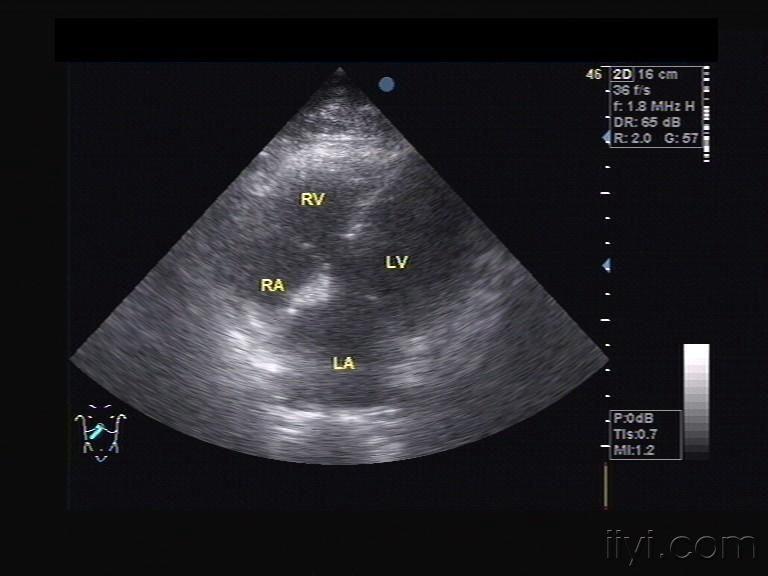

右位心超声,右位心的超声模板

右位心的超声模板

镜面右位心的超声模板

镜面右位心

超声心动

超声心动图